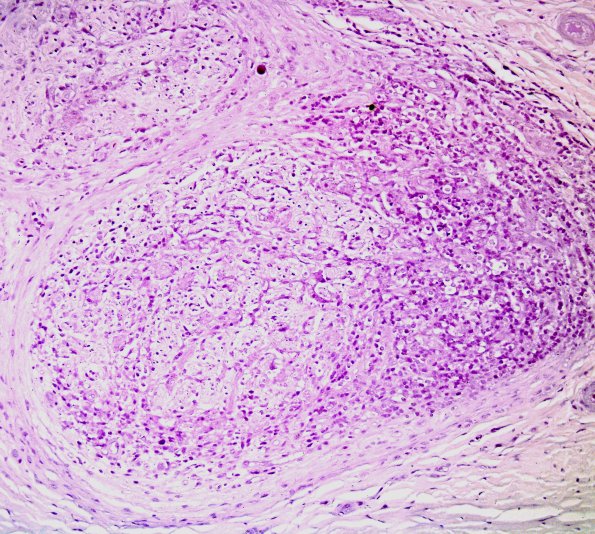

Washington University Experience | PERIPHERAL NEUROPATHY | 10 INFECTION | 4 Leprosy – Tuberculoid | 2B1 Leprosy, tuberculoid (Case 2) Fite 6

2B1-3 No organisms were identified with careful examination using oil immersion. (Fite stain)